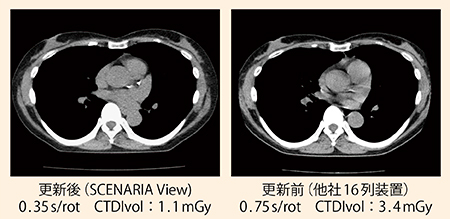

画像2:更新前後の縦隔条件画質比較

SCENARIA View撮影条件(左):120kVp,0.35s/rot,BP1.08,CTDIvol:1.1mGy 更新前の装置と比較し,1/3以下の低線量条件でも良好な画質が得られている。0.35s/rotでの撮影により,心臓のモーションアーチファクトも低減している。